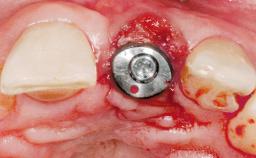

| Placement Protocol | Immediate implant placement |

| Socket Morphology | Single-root socket |

| Socket Integrity | Damage to one or more bone walls |

| Bone Volume | Damage to one or more socket walls |

| Esthetic Risk | Medium |

| Risk of Complications | High |